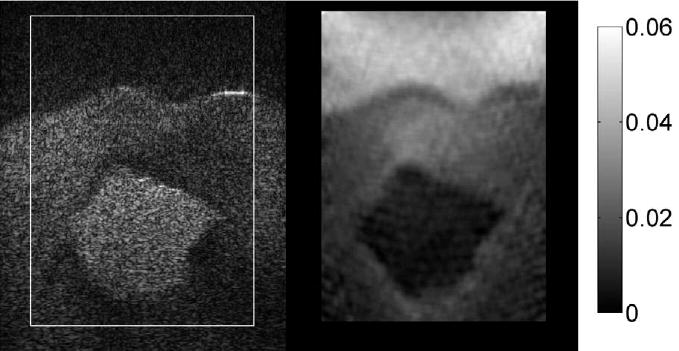

Figure 19 shows an MR image of a slice through the 14-mm diameter bound TM fibroadenoma. Figure 20 shows the corresponding MR elastogram corresponding to the gray scale depiction of the shear modulus. The method of data reduction to yield the MR elastogram is described in Weaver et al. (2001) and involves the generation of 100 Hz shear waves in the phantom and observing the propagation of those shear waves through the phantom.

Fig. 20.

Elastogram consisting of a gray-scale mapping of the shear modulus. (Scale values are in Pa.) The stiffer 14-mm diameter TM fibroadenoma (arrow) is seen as the brighter (stiffer) object; the TM subcutaneous fat is seen as the darker edges on the top, bottom and right side.

The MR elastogram (Fig. 20) seems to be far inferior in quality to all ultrasound elastograms of the breast phantom. However, it should be noted that the ultrasound elastograms are depictions of local strain values, whereas the MR elastogram depicts the shear modulus distribution. An ultrasound elastogram equivalent to the MR elastogram would be a gray-scale depiction of the storage modulus presumably derived from a local strain image. Obtaining such a depiction is well recognized as extremely challenging, and no attempt has been made to do such a depiction in the case of ultrasound elastograms of the breast phantom.